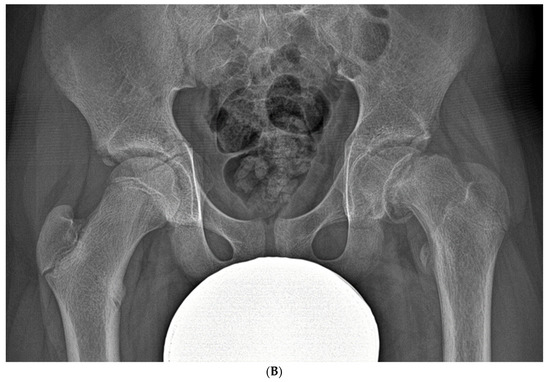

3.2.4. Exfoliation of Growth Plates

- Peck, K.; Herrera-Soto, J. Slipped capital femoral epiphysis: What’s new? Orthop. Clin. N. Am. 2014, 45, 77–86. [Google Scholar] [CrossRef]

- Georgiadis, A.G.; Zaltz, I. Slipped capital femoral epiphysis: How to evaluate with a review and update of treatment. Pediatr. Clin. N. Am. 2014, 61, 1119–1135. [Google Scholar] [CrossRef]